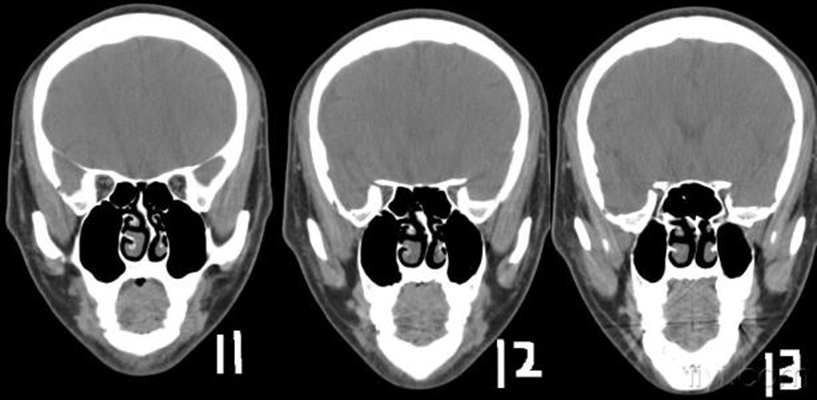

鼻中隔偏曲圖片

鼻中隔彎曲手術圖解 (7)

鼻中隔彎曲手術圖解 (8)

鼻中隔彎曲手術圖解 (9)